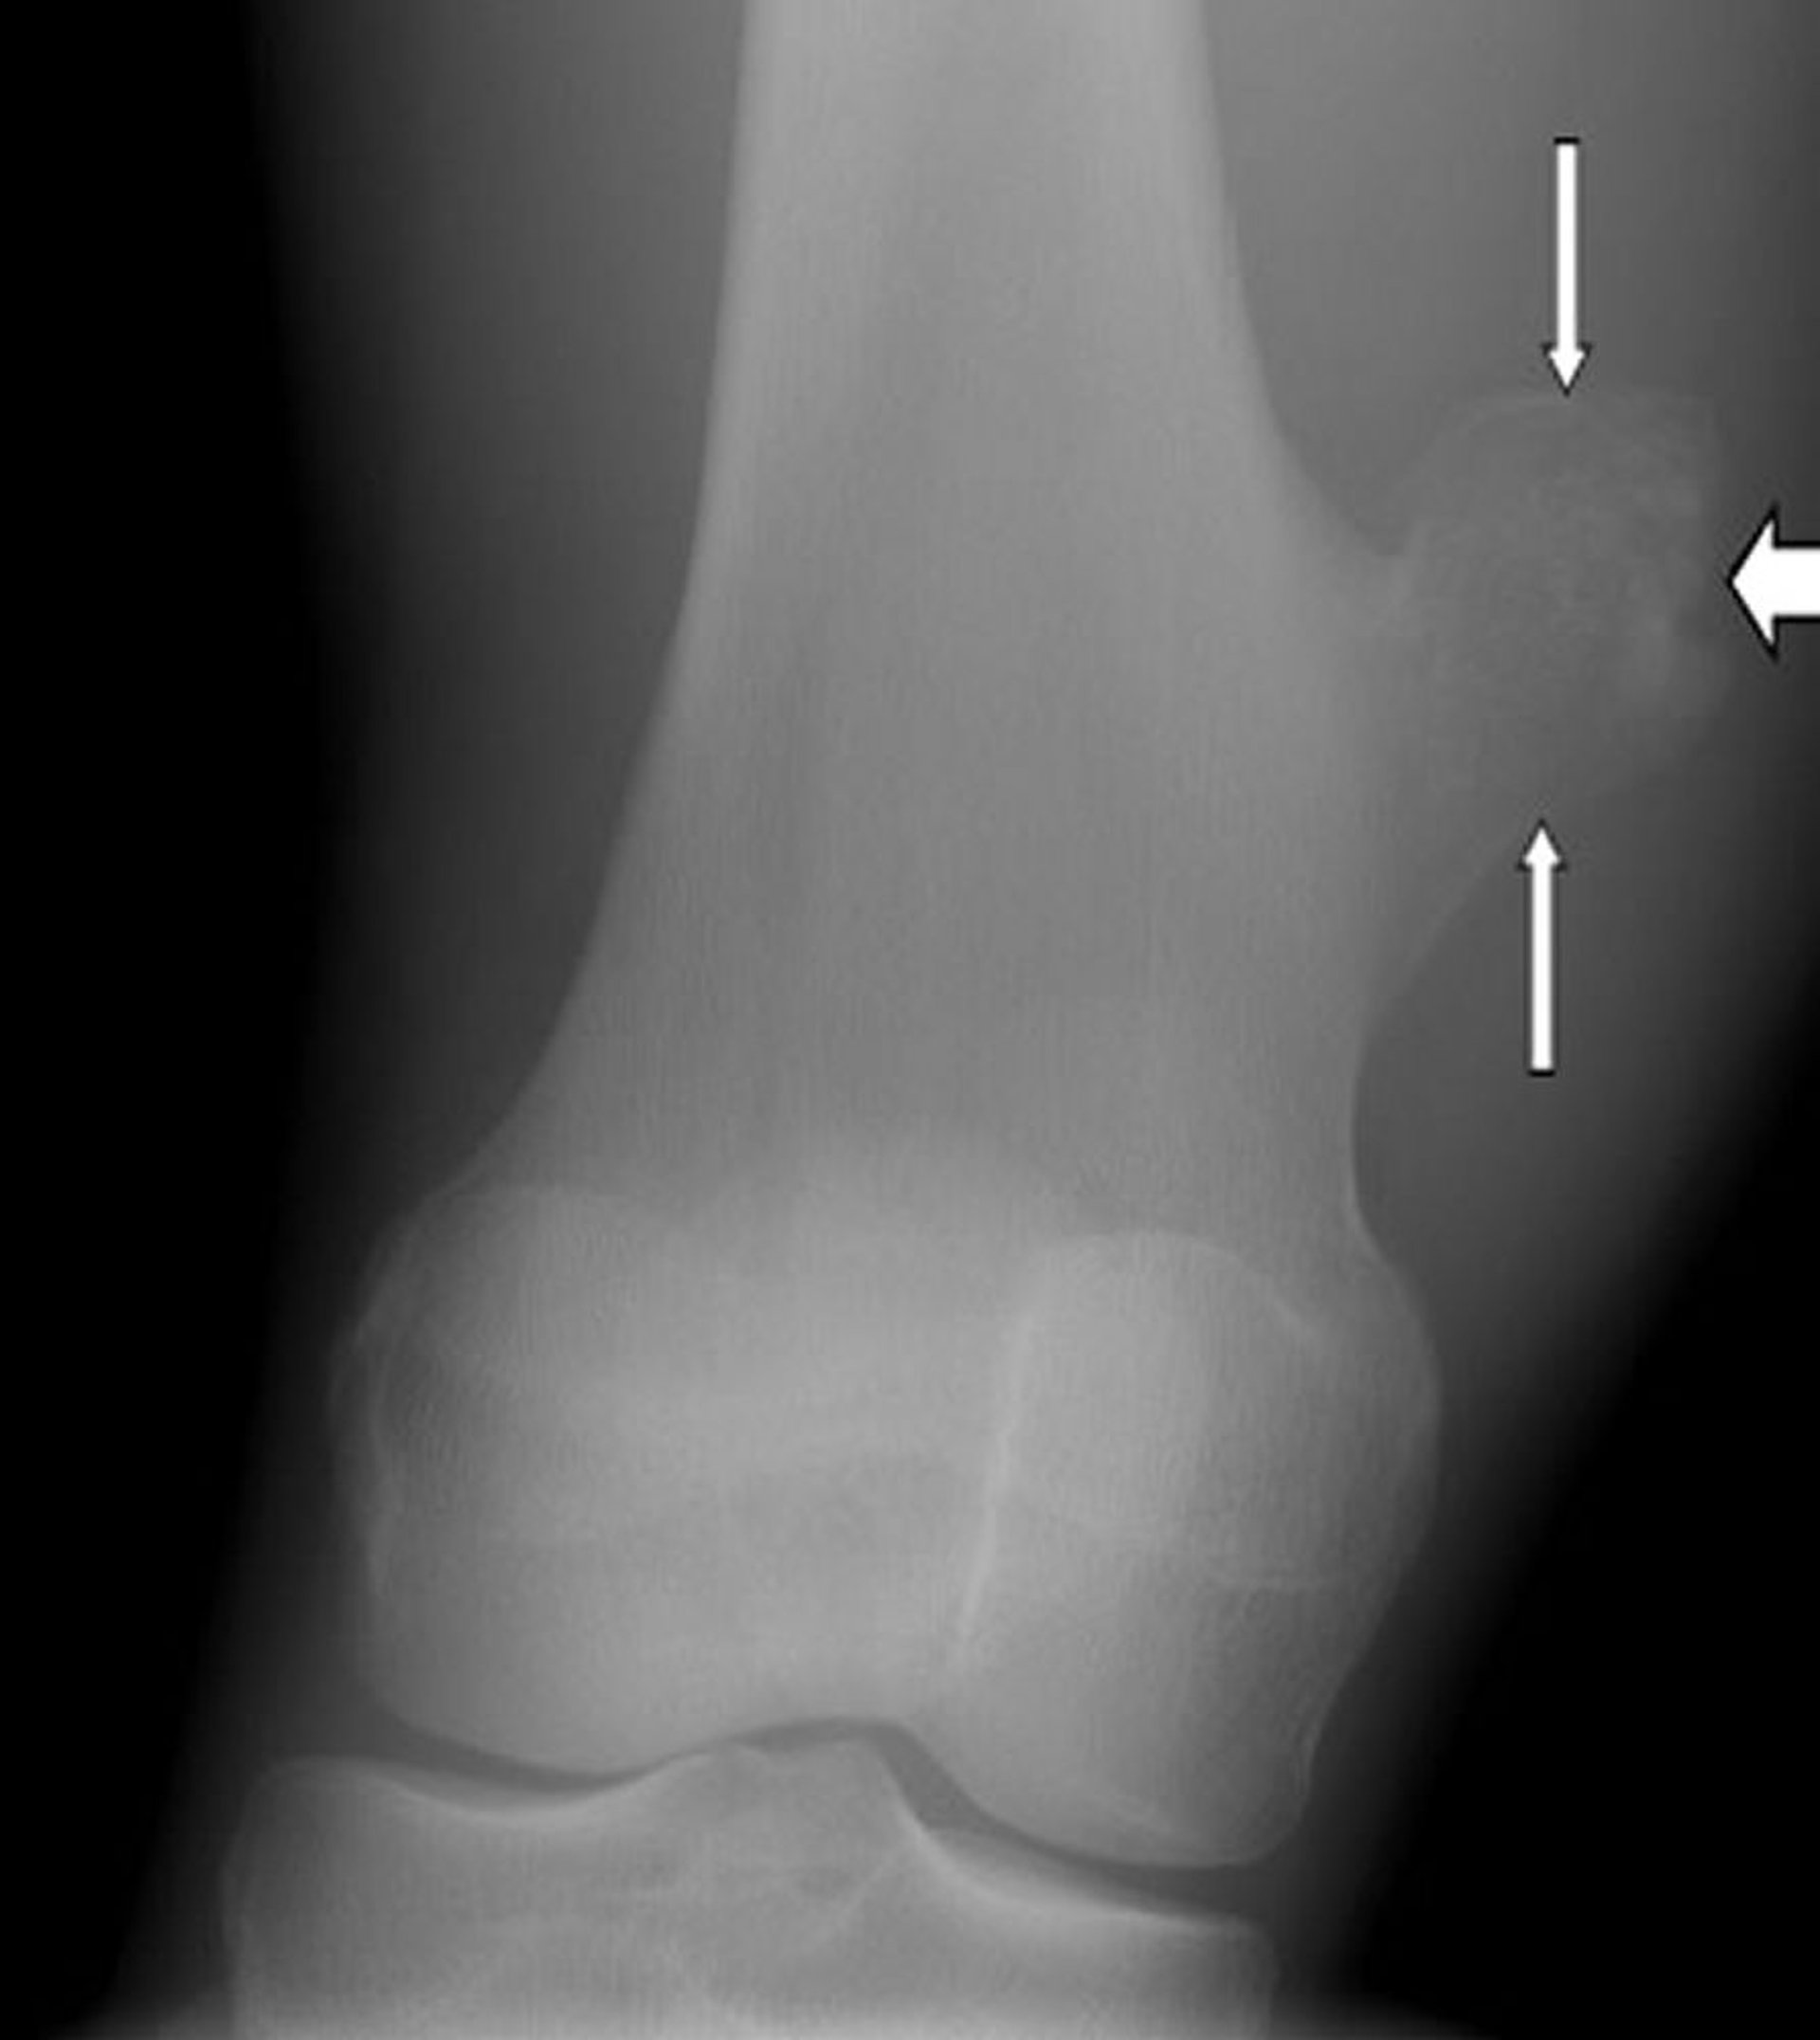

Ostéochondrome du genou

Cette radiographie du genou montre un ostéochondrome, l’excroissance située à la surface de l’os de la cuisse (flèches), juste au-dessus de l’articulation du genou.

Image publiée avec l’aimable autorisation des Drs Michael J. Joyce et Hakan Ilaslan.